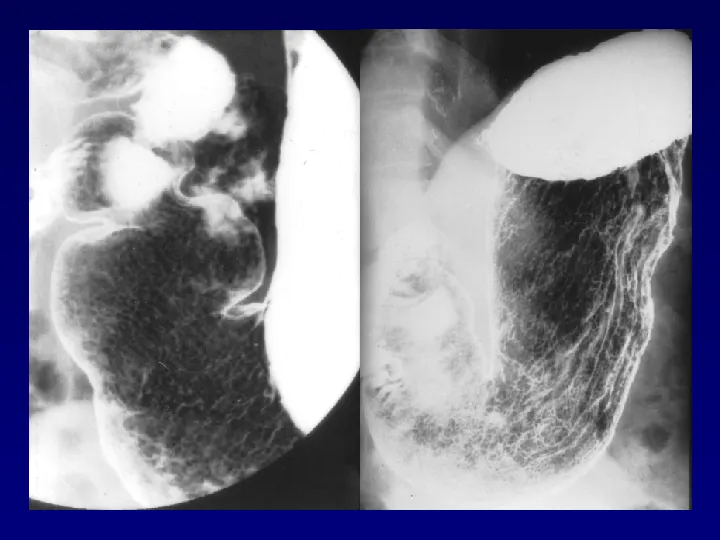

>【影像PPT】胃肠道钡餐检查的操作规范

【影像PPT】胃肠道钡餐检查的操作规范